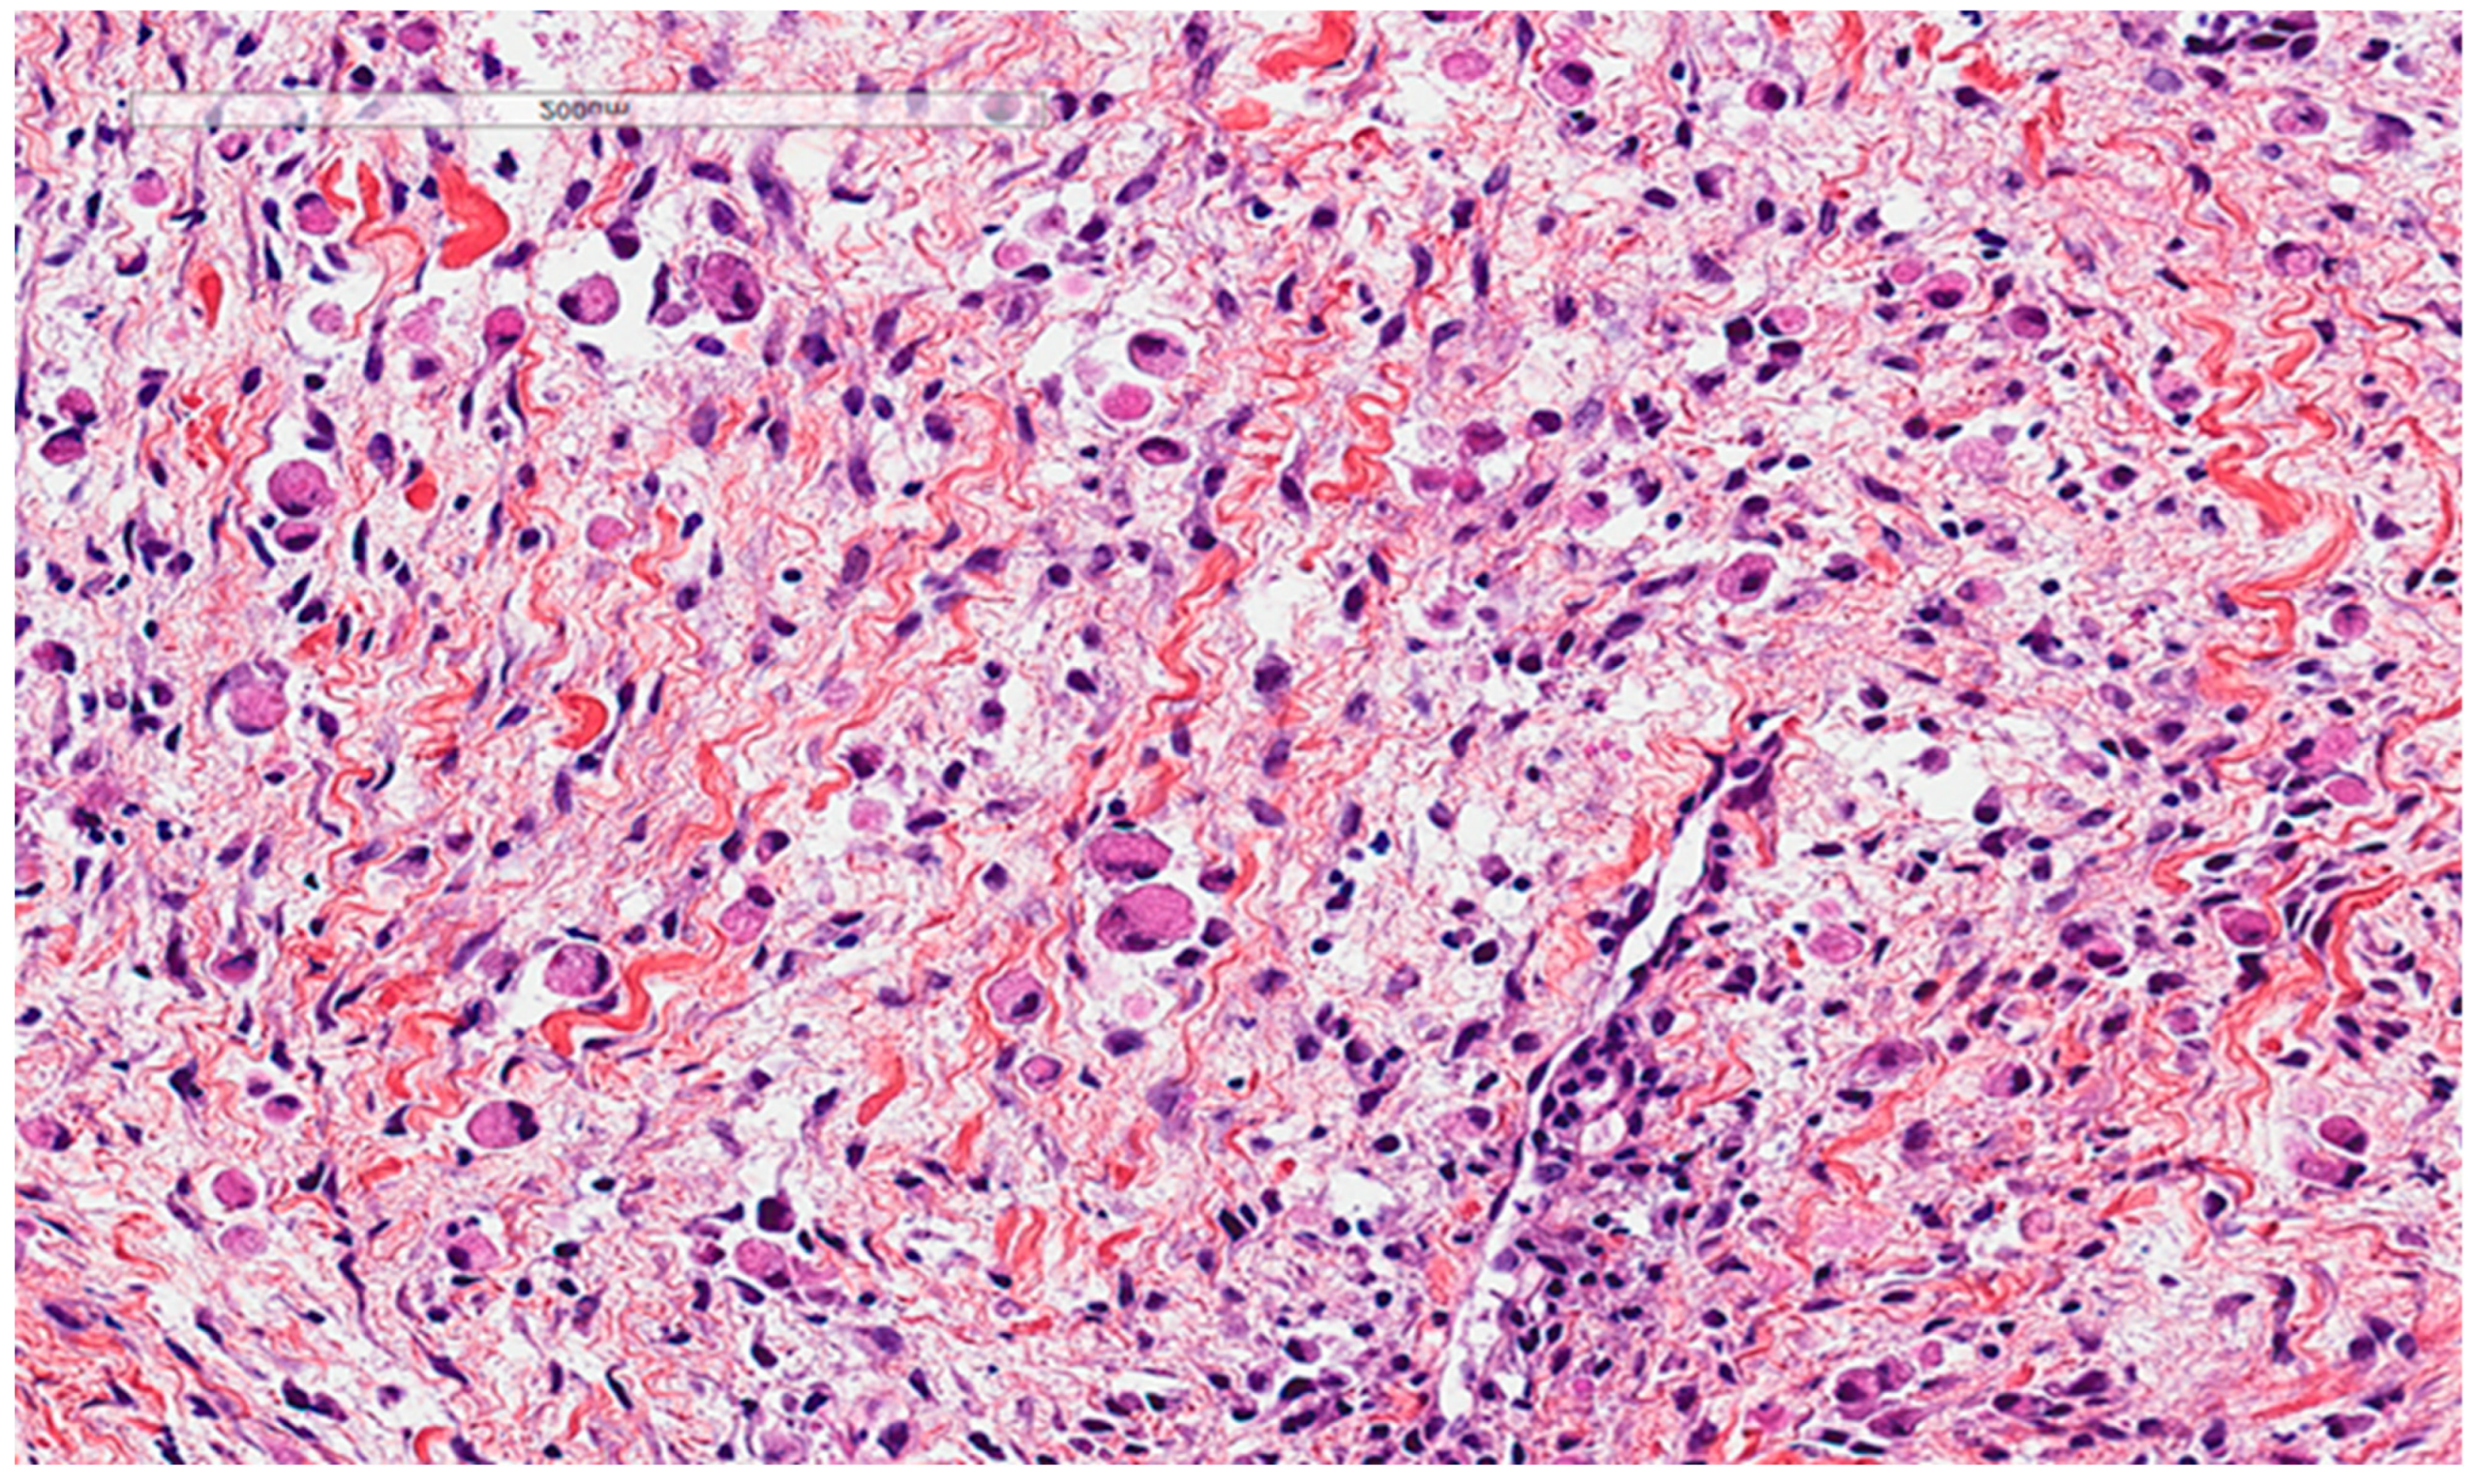

Malakoplakia is an inflammatory condition associated with macrophages that are unable to properly digest the phagocytosed bacterial material. It typically affects the urogenital region, but many organs can be affected. Microscopically, it is characterized by a histiocytic reaction with eosinophilic cytoplasm in the inflammatory background and, sometimes, by Michaelis–Gutmann basophilic inclusions which can be demonstrated by Von Kossa stain (Figure 3). It is positive for anti-CD68 and negative for anti-S100. In contrast, granular cell tumors (Figure 3), a benign tumor type of Schwann cell origin, also with wide anatomic distribution, presents positivity for both anti-CD68 and anti-S100, with homogenous eosinophilic cytoplasm and the presence of the so-called pustule-ovoid bodies of Milian (eosinophilic globules surrounded by a clear halo). It is commonly described in the head and neck and cutaneous tissues. It is sometimes associated with pseudoepitheliomatous hyperplasia of the overlying squamous epithelium that can be mistaken for a squamous cell carcinoma.

Figure 3.

Malakoplakia. (A). Malakoplakia is an inflammatory process consisting of macrophages with an abundant eosinophilic cytoplasm (hematoxylin, eosin, Safran). The lesion was found in a 60-year-old male patient who underwent a colonoscopy within the context of pre-renal transplant evaluation and was found to have this lesion as a perianal polyp that was removed by polypectomy. (B). The characteristic Michaelis–Gutmann basophilic inclusions are better highlighted by the Von Kossa stain. (C). Granular cell tumor with microgranular eosinophilic cytoplasm containing the pustule-ovoid bodies of Milian (eosinophilic globules surrounded by a clear halo). This lesion presented as a reddish skin nodule in a 48-year-old-female patient.